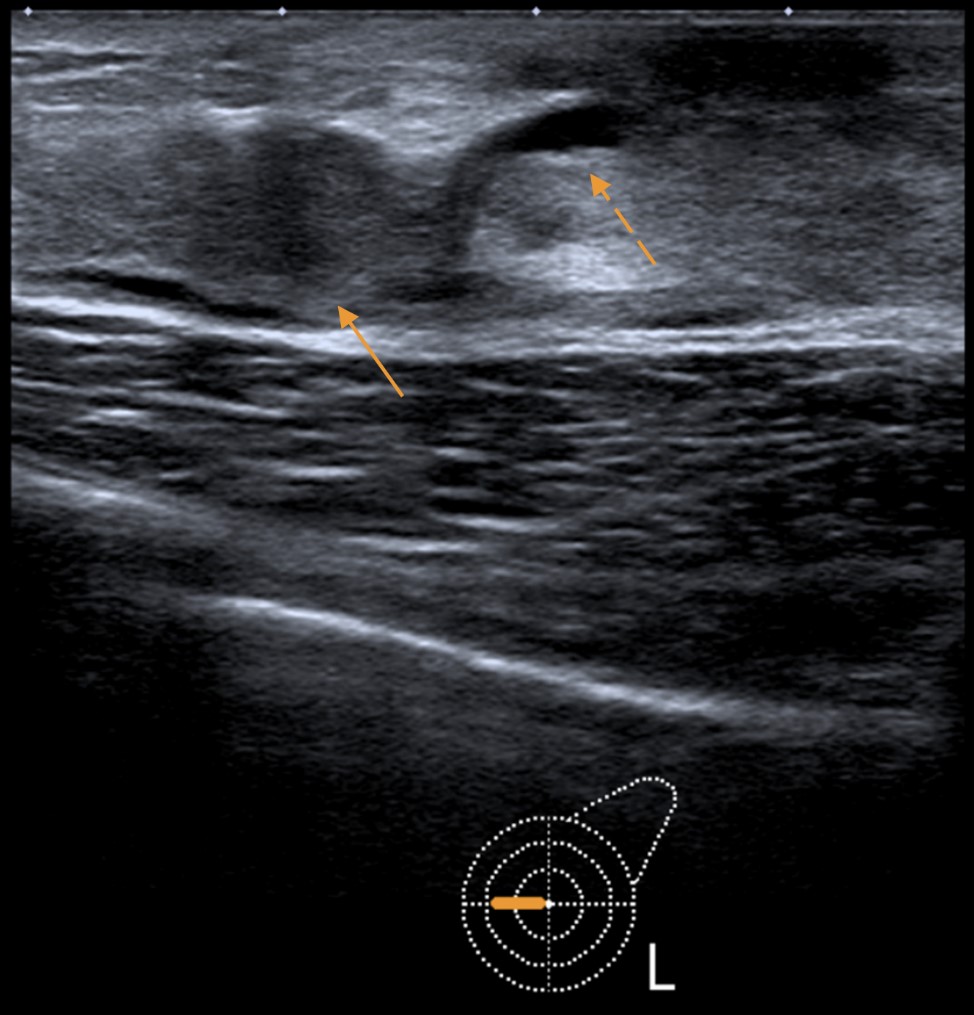

Breast ultrasound (Fig. 1) showed slight retroareolar duct ectasia (2.5 mm) in the left breast, and a 9 mm solid hypoechoic nodule in the transition of the inner quadrants, classified as a BI-RADS 4A lesion.

Figure 1: Breast ultrasound revealed a 9 mm hypoechoic, solid nodule (solid arrow), associated with slight duct ectasia (dashed arrow).